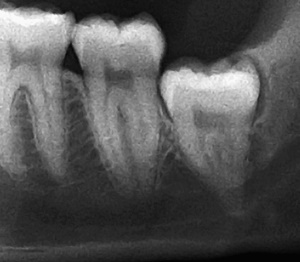

우리가 사랑니라고 부르는 것은 큰 어금니 중 세 번째 위치에서 제일 마지막에 나오는 치아입니다. 사랑니가 나올 때에는 첫사랑을 하듯이 아프다고 하여 붙여진 이름이라고 하는데요. 다른 이름으로는 ‘지치’라고 합니다. 지치는 사리를 분별할 수 있는 지혜가 생긴다는 뜻입니다.

사랑니는 보통 큰 어금니와 비슷하게 생겼습니다. 사랑니의 형태나 크기는 매우 다양하다고 하는데요. 보통의 어금니 보다 깊이 나기 때문에 빼기 어렵거나 절개를 통해 힘들게 빼야 하는 경우가 많습니다. 원래 사랑니는 음식물을 갈아 내기 위한 용도라고 하는데요. 이것은 치아의 퇴화 현상이라고 생각하시는 분들도 많이 계십니다.